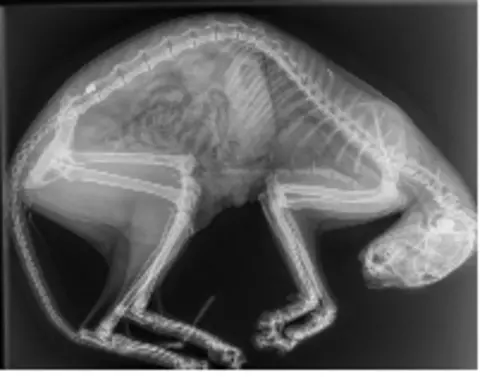

In Dorset, a 10-month old cat, Aura, was put to sleep after she was shot with an air weapon.

A pellet was removed from her after she was injured in Lytchett Matravers, near Poole, in February.